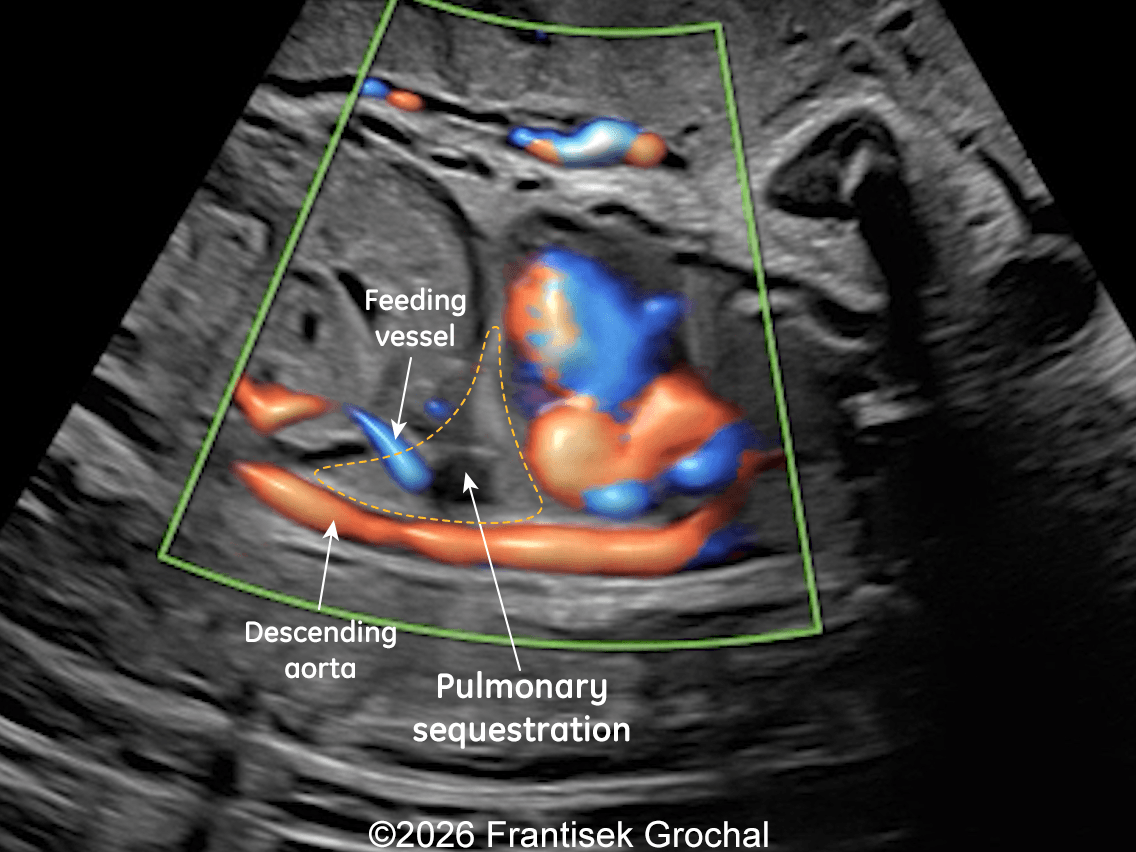

22+3 weeks of gestation – sagittal view demonstrating a well-circumscribed, triangular pulmonary sequestration; color Doppler imaging demonstrates a systemic feeding artery arising from the descending abdominal aorta.

Image 3 22+3 weeks of gestation – sagittal view demonstrating a well-circumscribed, triangular pulmonary sequestration; color Doppler imaging demonstrates a systemic feeding artery arising from the descending abdominal aorta.